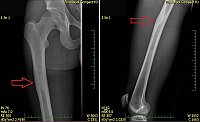

Obr. 1 Osteoidní osteom v rentgenovém obraze